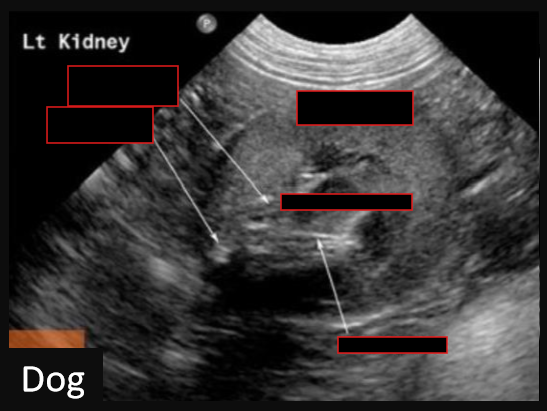

9

Label this frontal/dorsal view kidney ultrasound